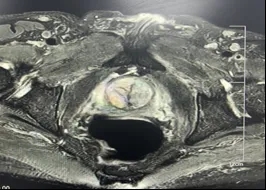

消融前

消融中

消融后即刻超声造影评估,呈“空洞状”

在术中,经验丰富的郭建琴主任医师团队借助先进的经直肠双平面超声探头精准引导,通过一根直径仅1.4mm的微波消融针,经会阴部精准穿刺至前列腺增生部位——直达病灶深处,利用超声实时监控,医生精准的将微波针在病灶中移动,术中不能有丝毫差错,在保证不伤到尿道、外周组织、血管及神经的同时,让微波能量精准的使增生组织凝固性坏死,整个过程创伤小,极大降低了对患者身体机能的影响。